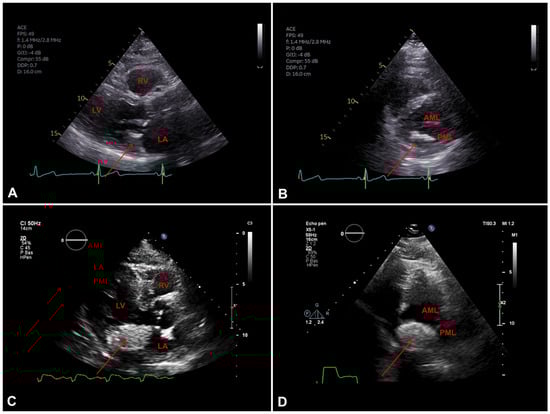

Figure 6.

A. Transothoracic echocardiography (TTE) parasternal long axis view showing mitral annular calcification (MAC) (arrow), LV: left ventricle; LA: left atrium; RV: right ventricule. B. TTE parasternal short axis view showing mitral valve with MAC (arrow), PML: posterior mitral leaflet; AML: anterior mitral leaflet. C. TTE parasternal long axis view showing (arrow), LV:left ventricle LA: left atrium;RV: right ventricule. D. TTE parasternal short axis view showing mitral valve with caseous calcification (arrow), PML: posterior mitral leaflet; AML: anterior mitral leaflet.

Multimodal imaging

On transthoracic echocardiography (TEE), appears as a round calcification, with well-defined brightened edges corresponding to an echodense periphery, and a central echolucent area corresponding to the central liquefaction area. Colour Doppler shows a lack of flow inside the central zone [

1,

7]. Differences between mitral annular calcification and caseous calcification on TEE are summarised on

Table 2 and illustrated in